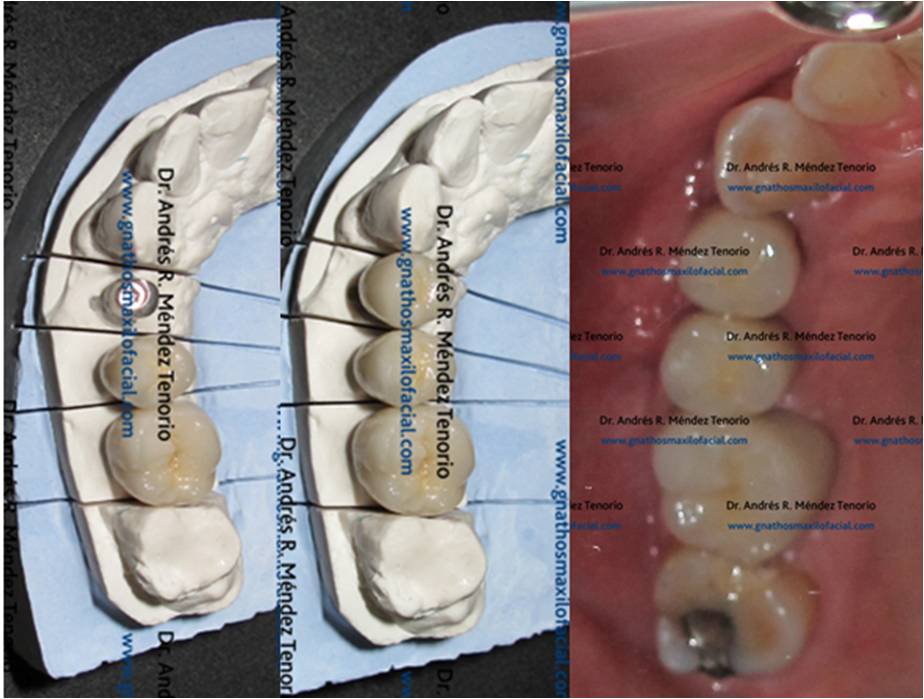

| Modelo de laboratorio con coronas de porcelana sobre dientes naturales adyacente a prótesis sobre implante dental | |

| Rehabilitación terminada | |